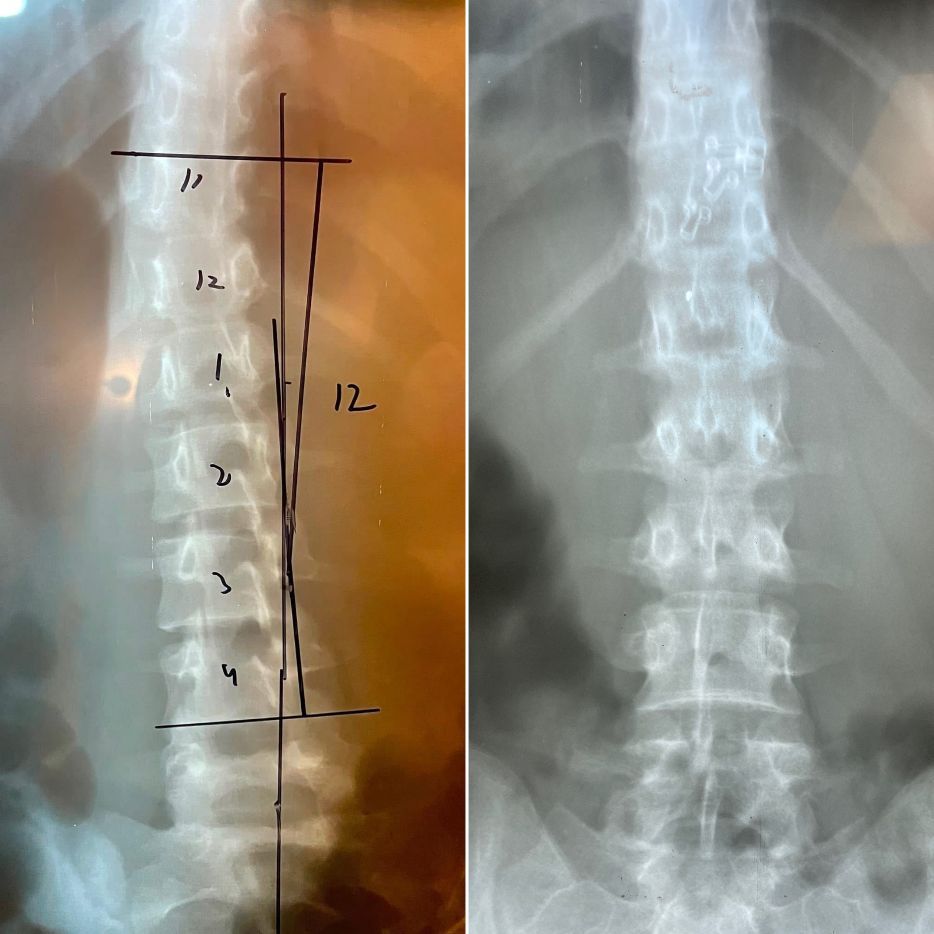

Before

13 degrees and spine shifted to left in 13 year with progressive scoliosis

After

8 degrees and spine is more centered 3 months later

12 degrees with left spine shift

6 degrees with centered spine after 3 months